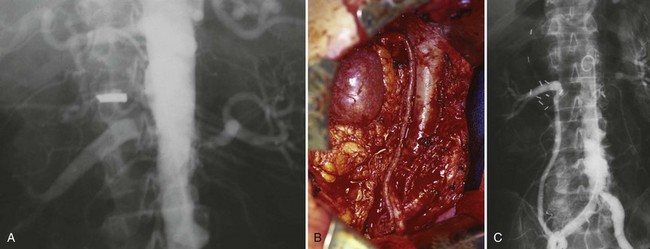

Since its introduction in the early 1970s, renal artery embolization (RAE) has been employed for palliation of inoperable renal tumors, to control bleeding, and as part of multimodal treatment of hypervascular metastatic disease (Almgard et al, 1973). In addition, RAE is used as a preoperative adjunct to resection of locally advanced renal tumors, with or without metastases (Paster et al, 1975) (Fig. 54–15).

Figure 54–15 A, Aortogram in a patient with a left hypervascular renal mass. Note the pooling of contrast medium in the upper pole. B, Left selective artery angiogram before coil placement. C, Aortogram after coil placement demonstrating abrupt cutoff of flow from the left renal artery.

Proposed benefits of preoperative RAE include shrinkage of an arterialized tumor thrombus to ease surgical removal, reduced blood loss, facilitation of dissection due to tissue plane edema, ability to ligate the renal vein before the renal artery at time of nephrectomy, and modulation of the immune response (Klimberg et al, 1985; Bakal et al, 1993; Kalman and Varenhorst, 1999; Schwartz et al, 2007; Wotkowicz and Libertino, 2007; Wszolek et al, 2008). Ligation of the renal vein before the renal artery is useful in the setting of hilar tumors, tumors with significant medial extension, or considerable perihilar adenopathy (Schwartz et al, 2007; Wotkowicz and Libertino, 2007; Wszolek et al, 2008). Before ligating the renal vein, one should characterize the completeness of embolization to prevent unnecessary blood loss in cases of incomplete embolization. In the senior author’s experience this assessment can be made by evaluating renal venous return during surgery. In addition, angioembolization can also be useful for renal tumors associated with large arteriovenous malformations that are having a deleterious hemodynamic impact (Figs. 54-16 and 54-17).